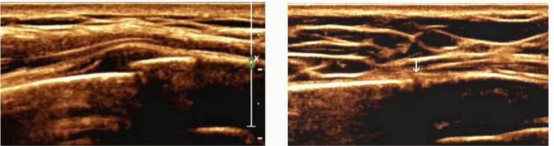

3、超声在外周神经的应用:肌骨超声对于神经的评估分辨率高,可清晰显示外周神经的神经束、神经束膜、神经外膜结构、神经粗细以及与周围组织的关系,准确诊断周围神经炎及外周神经损伤的原因、部位。主要扫查的外周神经包括:上肢的臂丛神经、正中神经、桡神经、尺神经;下肢的股神经、坐骨神经、胫神经、腓总神经、股外侧皮神经。常见疾病:神经损伤、神经卡压、神经炎、周围神经源性肿瘤等。

图3 腕管综合征